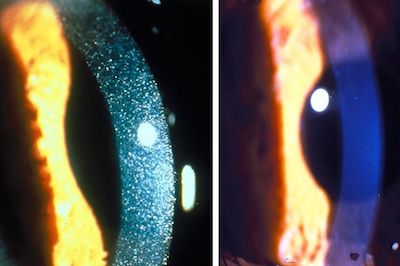

- Photophobia (lights hurting the eyes) due to corneal crystals

- Visual impairment due to retinopathy (involvements of the back of the eyes)